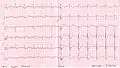

RBBB with associated first degree AV block

RBBB with associated first degree AV block RBBB with associated tachycardia